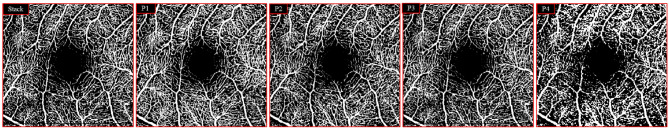

Methods: Healthy subjects were imaged using the SPECTRALIS OCT-A Module (Heidelberg Engineering) with the following scanning protocols: 10ºX10º-512 ART 7 [P1], 10ºX10º-256 ART 5 [P2], 10ºX10º-512 ART 5 [P3], and 15ºX10º-256 ART 5 [P4], all centered on the macula. Vessel perfusion density (VPD) and vessel length density (VLD) of the superficial vascular complex (SVC) were calculated using ImageJ software to evaluate the differences between scanning patterns. Three additional 10ºx1º, ART 7 high-density images were also obtained using the in-built software (SP-X1701 Update 3, based on Heyex Software Version 1.9.215.0 H) in the macular area and the VPD and VLD for all the three10ºx1º pattern size images with the corresponding area of pattern 1 image[P1]. Two retinal specialists conducted a blind qualitative assessment of the foveal avascular zone and image quality.

Results: Twenty eyes from 20 consecutive healthy patients were included in the study. The mean VPD for P1, P2, P3, and P4 were 35.60, 31.67, 31.18, and 31.16, respectively. Mean VLD for P1, P2, P3, and P4 were 7.54, 5.86, 6.74, and 4.40, respectively. Significant differences were found between P1 and the other patterns for both the VPD and VLD, but not between P2, P3, and P4. VPD and VLD for 10ºx1º high-density images were 33.20 and 4.61, respectively, with significant VLD differences compared to P1, but not for VPD. P1 scored the highest and P4 the lowest in the qualitative assessments.

Conclusions: The 10ºX10º-512 ART 7 pattern showed statistically significant qualitative superiority and appeared optimal for blood flow detection with reduced noise in quantitative assessments.